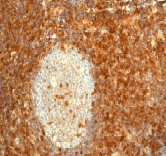

Anti-CD99 antibody [EPR3097Y](ab75858)

Rabbit Recombinant Monoclonal CD99 antibody. Suitable for IHC-P, IP, WB, ICC/IF, Flow Cyt (Intra) and reacts with Human samples. Cited in 2 publications.

Applications Flow Cyt (Intra), ICC/IF, IHC-P, IP, WB

Species Reactivity Human